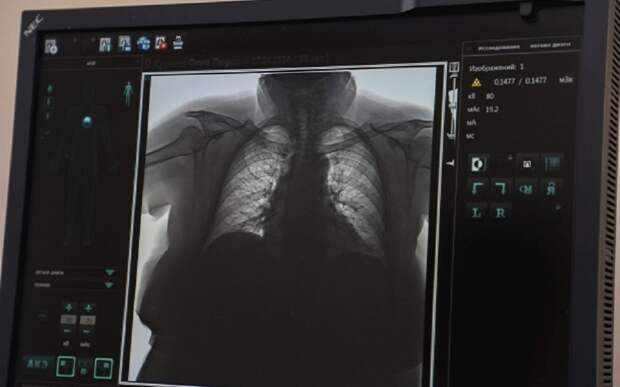

По словам медика, коронавирус вызывает массовый характер повреждения клеток во всех органах и системах человека. Разрушая эпителий в дыхательных путях, вирус вызывает воспаления, от этого ткани могут многократно утолщаться и терять свою воздушность. Под микроскопом специалисты могут не найти ни одной нормальной клетки, во всех сосудах имеются какие-либо изменения: или тромбы, или увеличение проницаемости сосудистой стенки.

Человек, который перенесёт COVID-19, рискует, что часть его лёгкого станет полностью безвоздушной и больше никогда не сможет выполнять свои функции, − рассказывает Григорий Снигура.